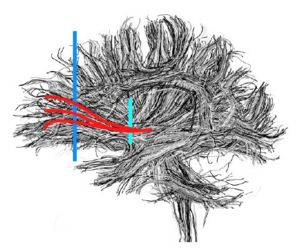

Arcuate Fasciculus

These labelmaps ('caseD00XXX-FS-arcuate-final.nhdr') were created using automatic gray matter parcellation in Freesurfer and coregistered in Slicer to corresponding DTI dataset. The labelmaps were dilated in Slicer to increase coverage of gray matter.

Figure 13. Gray matter ROIs (right side) in 3D